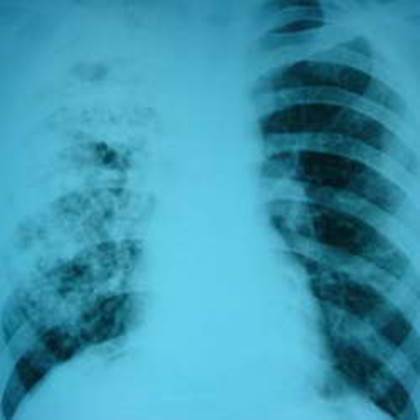

Лёгкие человека, поражённые туберкулезом.